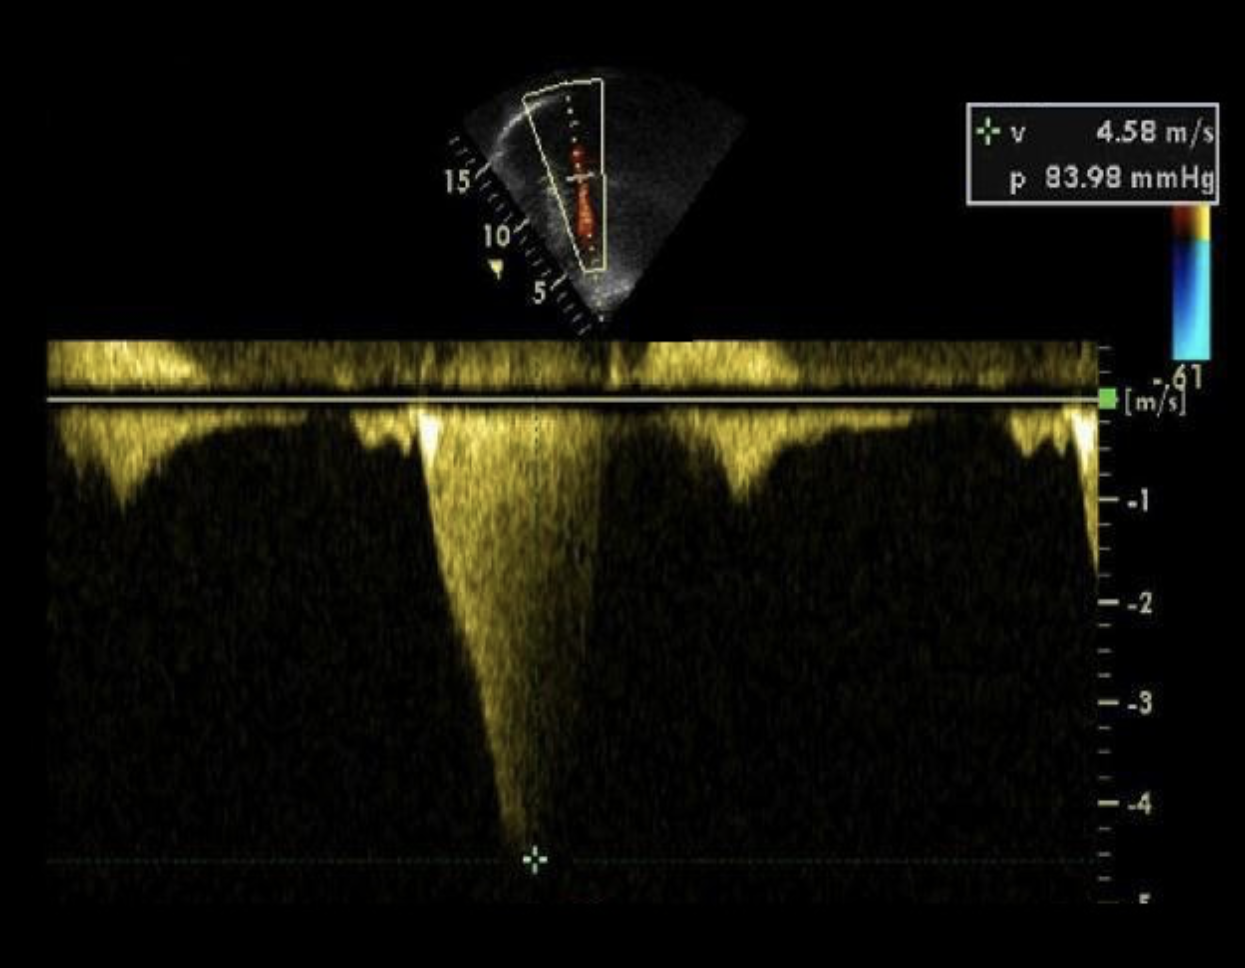

Which left heart abnormality will cause the aortic CW Doppler flow pattern demonstrated in the image?

HCM

The Doppler tracing of the LVOT seen with HOCM is said to resemble?

Dagger